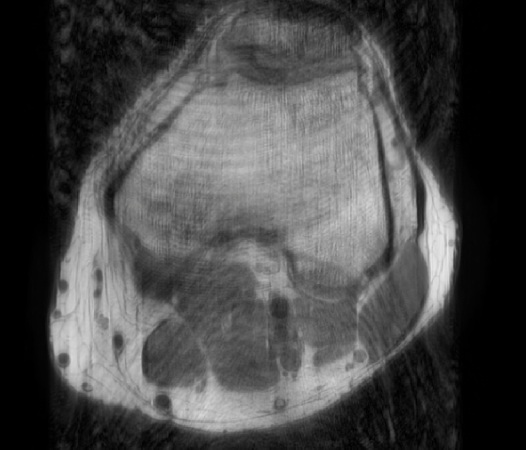

In the example below, only one fifth of the required MR radiofrequency signals is recorded. This results in a five times faster acquisition, with a subsampled k-space (top left) and inherent image artifacts after standard reconstruction (top right).

Basic compressed sensing principle